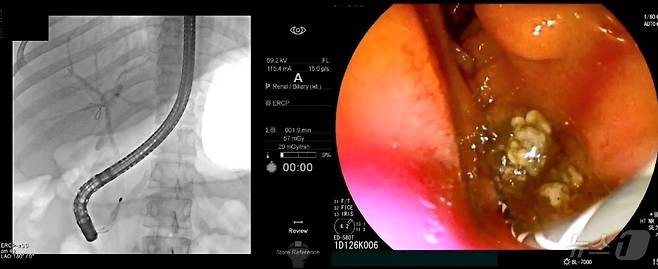

초음파내시경으로 담관결석이 관찰되면 내시경적 역행성 담췌관조영술(ERCP)을 통해 담관결석을 제거한다. ERCP는 특수내시경과 방사선을 이용한 시술로, 내시경을 십이지장까지 삽입하고 십이지장 유두부를 통해 담관에 관을 넣고 조영제를 주입해 담석의 정확한 위치를 확인한다. 이후 미리 넣어놓은 가이드선을 따라 바스켓 또는 풍선 기구를 담관으로 넣어 담석을 제거한다. ERCP로 담관결석을 제거한 뒤에도 재발을 막기 위해 담낭담석을 제거하는 담낭절제술이 필요하다.